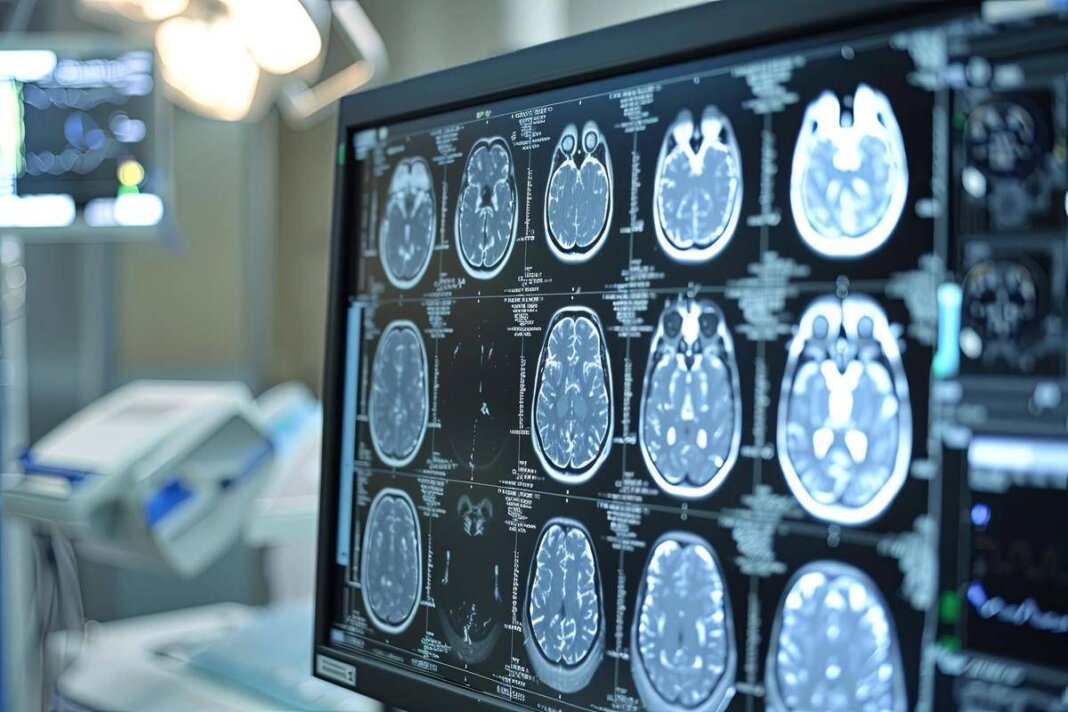

Asundexian ha ottenuto la designazione fast track dalla Food and Drug Administration degli Stati Uniti come potenziale trattamento per la prevenzione dell’ictus nei pazienti con ictus ischemico non cardioembolico, ricorda la nota. Tuttavia – si legge – va sottolineato che asundexian è ancora un farmaco sperimentale e non è stato ancora approvato da alcuna autoritĂ sanitaria. Lo studio Oceanic-Stroke ha analizzato efficacia e sicurezza di asundexian, inibitore orale del Fattore XIa, somministrato alla dose di 50 mg una volta al giorno, per la prevenzione dell’ictus ischemico in pazienti che avevano recentemente avuto un ictus ischemico non cardioembolico o un attacco ischemico transitorio (Tia) ad alto rischio. Il trattamento è stato valutato in combinazione con la terapia antipiastrinica standard. Si tratta di uno studio multicentrico e internazionale, randomizzato, controllato con placebo, in doppio cieco, a gruppi paralleli e guidato dal numero di eventi, che ha arruolato oltre 12.300 pazienti.Â